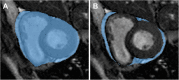

Fig. 1

Segmentation of the pericardium (A) with subsequent subtraction of the epicardium (B) to obtain an estimate of epicardial adipose tissue volume in an image obtained from a cine sequence in short axis acquired on an open-bore MR scanner in a 44-year-old male patient referred for bariatric surgery